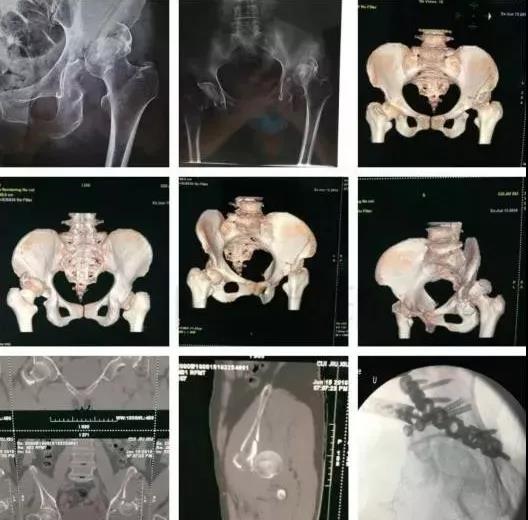

3)髋臼骨折(伤后5-7天)

- 人体最大的负重关节,精确复位可达到关节的最佳匹配,确保正常力学性能;

- 影像学移位程度大,不匹配>2mm--手术;

- 髋关节脱位,髋臼后壁骨折并股骨头骨折,复位后关节仍然不稳,或关节腔有游离骨块--手术。

并发症:异位骨化18-90%;股骨头坏死3-9%